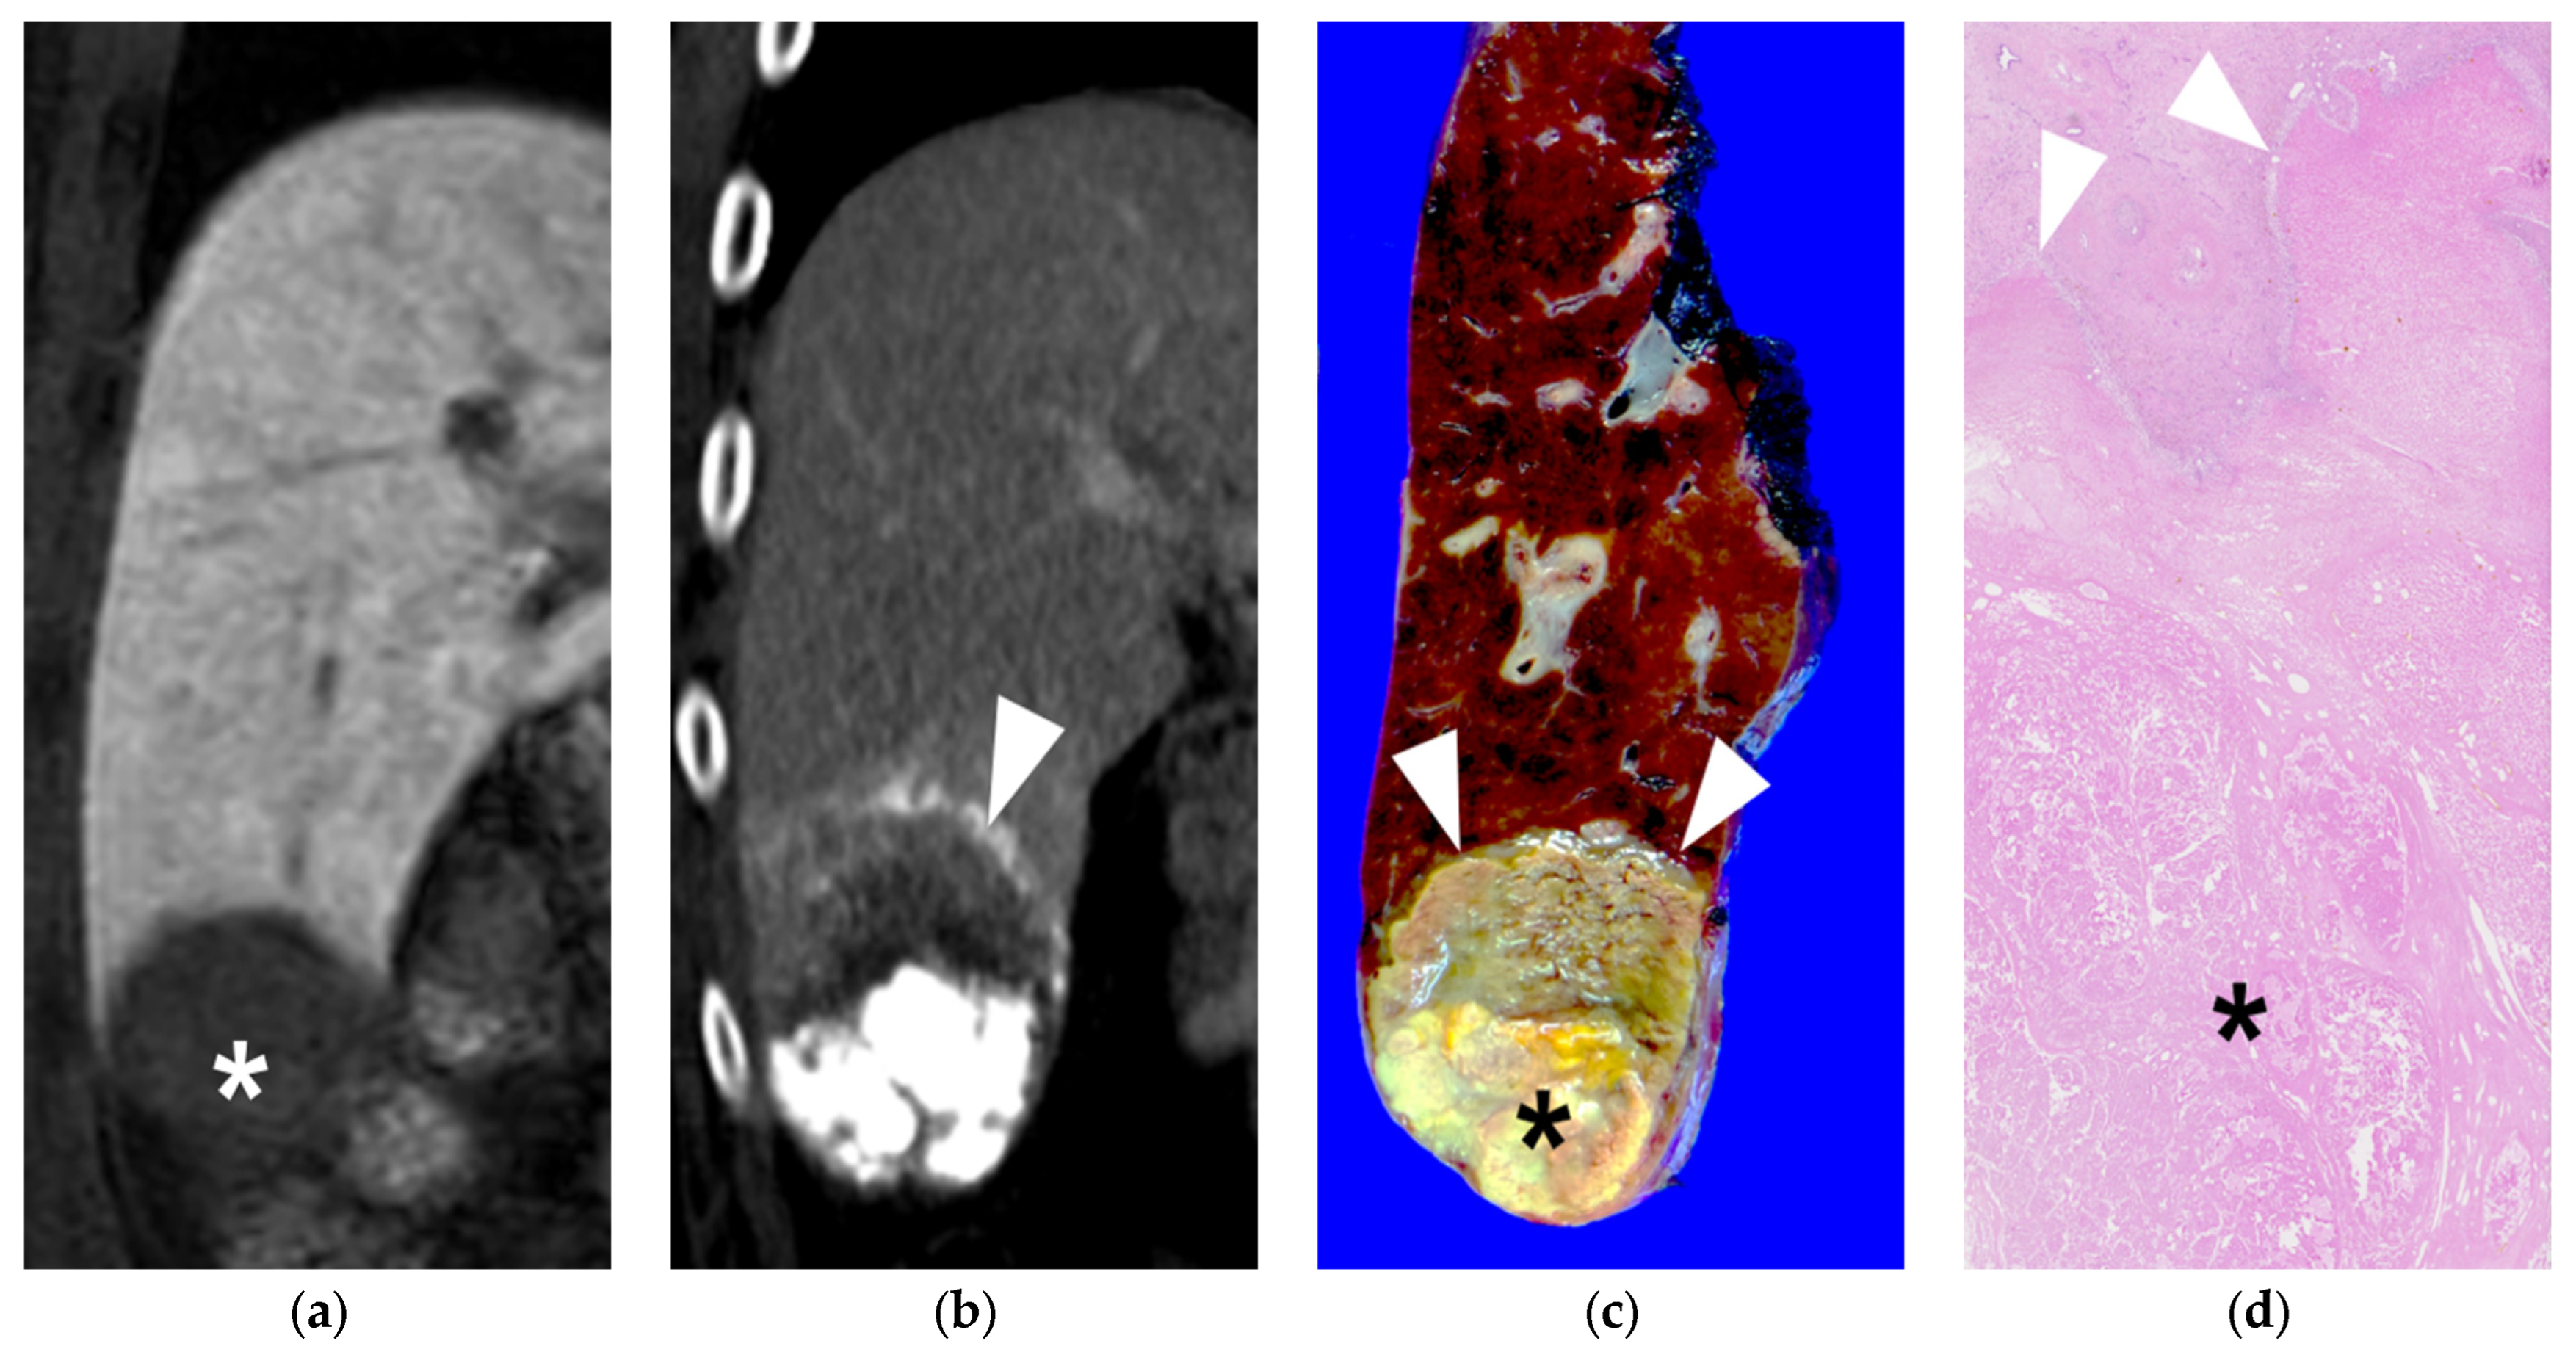

3.2. Radiological and Pathological Outcomes